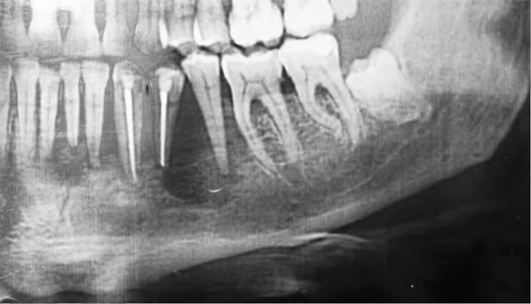

Фото Рак Нижней

Фото Рак Нижней 115 фото